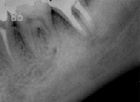

歯の根っこに膿ができて骨が溶けている症例です。

下記症例では歯を支えている骨が大幅に溶けて(黒く写っている部分)グラグラの状態で腫れた状態でした。下歯槽管(大きい神経や血管がある)近くまでバイ菌が忍び寄っています。大学教育では歯を抜くように教わりました。

薬で治す治療法を用いることによって骨が再生し、しっかりと噛める歯によみがえることができました。

| 歯を支えている歯が大幅に溶けて(黒く写っている部分)グラグラの状態 | 3Miix-MP法(R)により骨が再生し、歯のぐらつきが無くなっています |